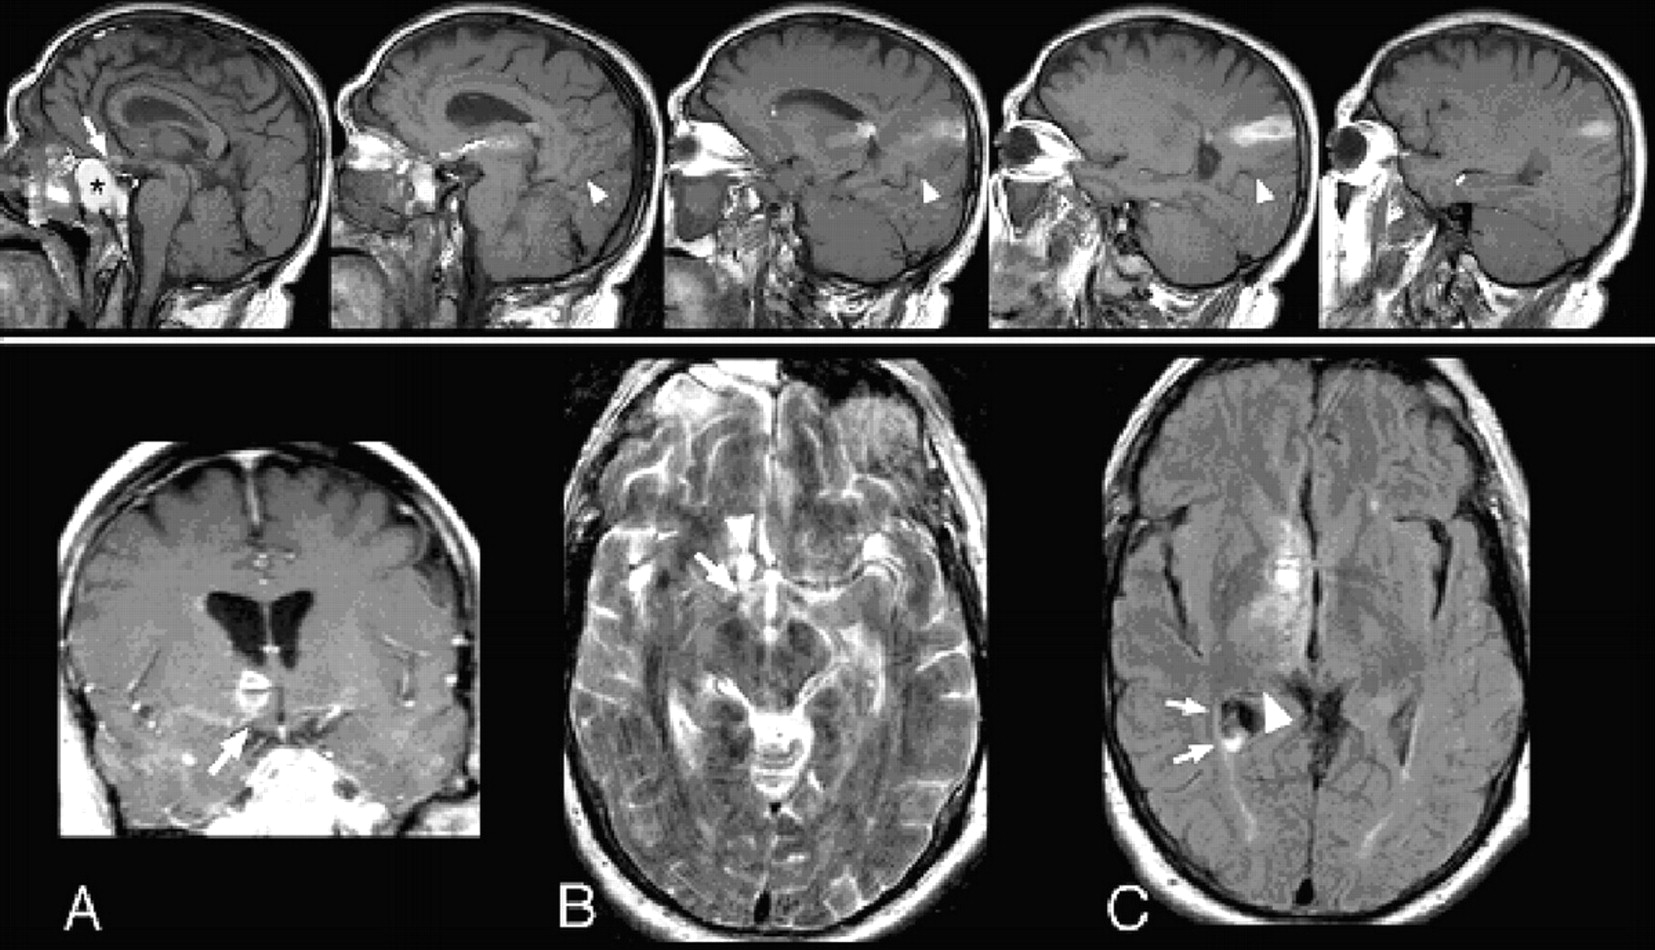

图。未上面板(左到右):节能矢状T1影像显示导管留下了一个不规则的线,一串出血(视为hyperintense信号)的入口点在蝶鞍上蝶窦前(最左边的形象;额叶箭头),通过丘脑,和通过侧脑室后上的右顶叶。蝶窦内可见出血(最左边的图像;黑色星号)。上方的导管小道跑parieto-occipital裂缝(箭头),因此不涉及枕叶。有一个小的集合亚急性血的提示下角(最右边的图片)。底板:(A)右额叶出血是立即优于右侧视神经束(T1增强冠状图像);(B)对视神经束显示异常增加信号(箭头)相邻导管小道(箭头;T2轴向图像); (C) the optic radiations (arrow) and lateral geniculate (arrowhead) are not within the catheter trajectory and are thus spared (FLAIR axial image).